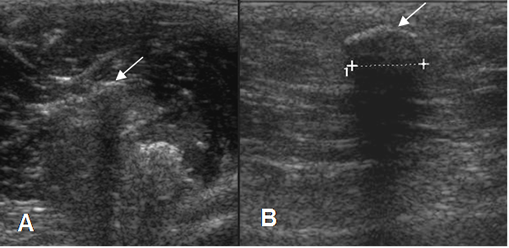

Fig 17. Fibrosis muscular.

A y B: Ecografía. Lesiones musculares de evolución crónica, identificadas como zonas hiperecoicas, que producen sombra acústica.